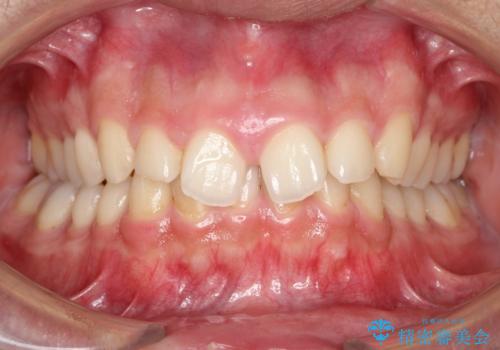

再矯正症例 前歯のガタガタと噛み合わせのズレをマウスピースで治した症例